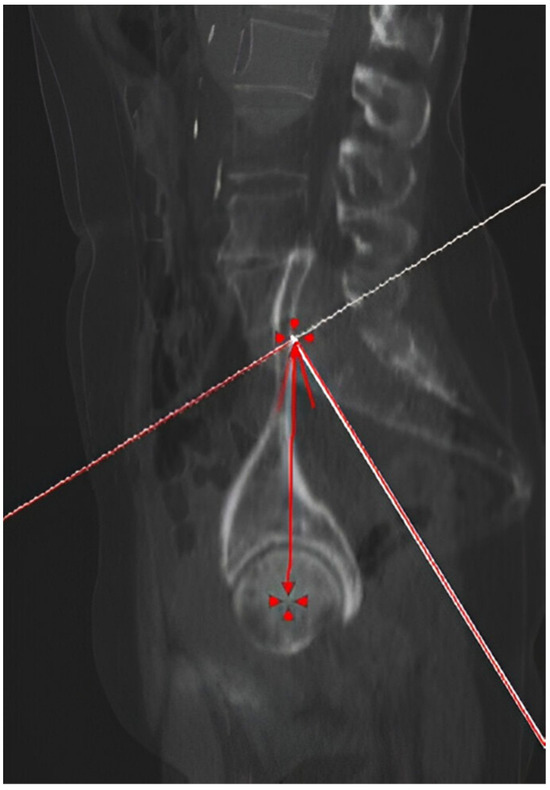

2.2. Measurements

| Femoral Version | 16.00° ± 4.53° (15.22°–16.78°) | 13.16° ± 4.37° (12.31°–14.01°) | 0.0001 |